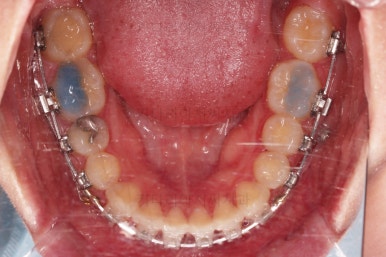

초진 시 입안의 모습을 보실게요.

결국은 앞니 사이에 틈이 생겼기 때문에 이같은 문제점을 인지하시고 내원하셨던거죠.

이번 환자분의 경우는 치아 결손 부위의 잇몸뼈도 양호했고 공간도 그리 크진 않았으며 윗니는 갯수가 1개 부족해도 교합을 맞추는데 문제가 거의 없기 때문에 시간이 좀 더 들더라도 임플란트 없이 앞니 사이 틈과 결손부위 틈새를 모아보기로 했어요.